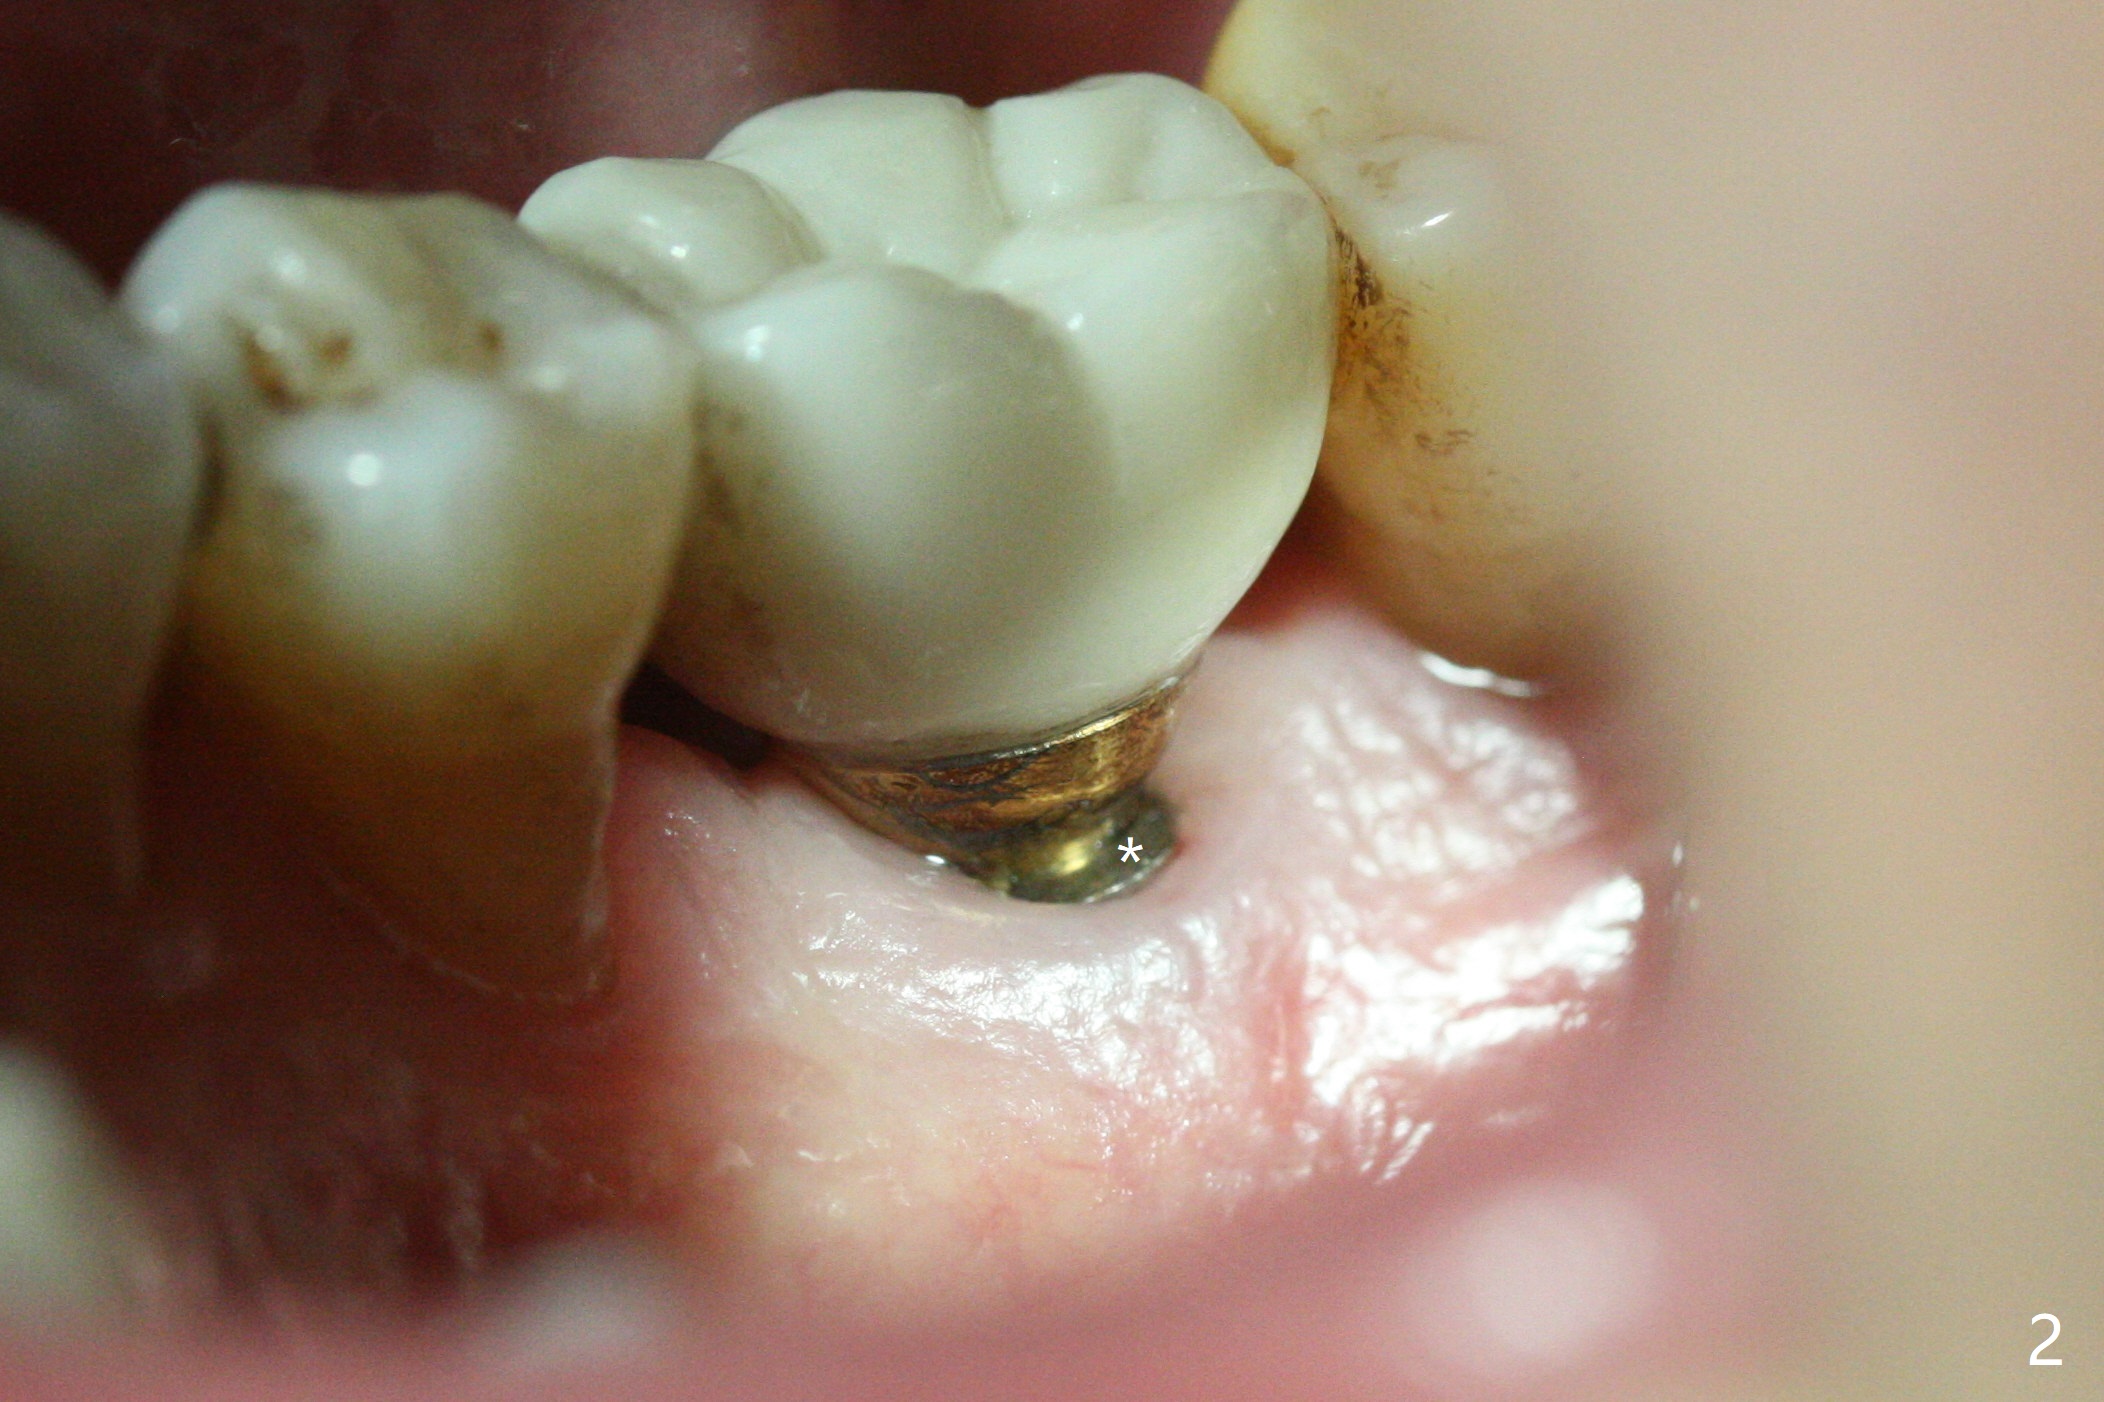

A 64-year-old man returns with history of a lump in the right submandibular region. Biopsy in a medical clinic shows inflammation. The implant crown at #30 has been cemented for ~ 4 years (Fig.1 (A: abutment)). The lingual plateau of the implant is exposed for 1-2 years asymptomatic (Fig.2 *). There is no deep lingual pocket when the crown and abutment are removed (Fig.3). Flap surgery confirms microthread exposure (circumferential, Fig.4). After removal of the microthreads with diamond bur (Fig.5), allograft (Fig.6 *), 6-month collagen membrane and a 6.5x5(3) mm healing abutment are placed. Following suturing, periodontal dressing is applied. The site remains asymptomatic 3 months postop, when an implant is placed subcrestal at #3.